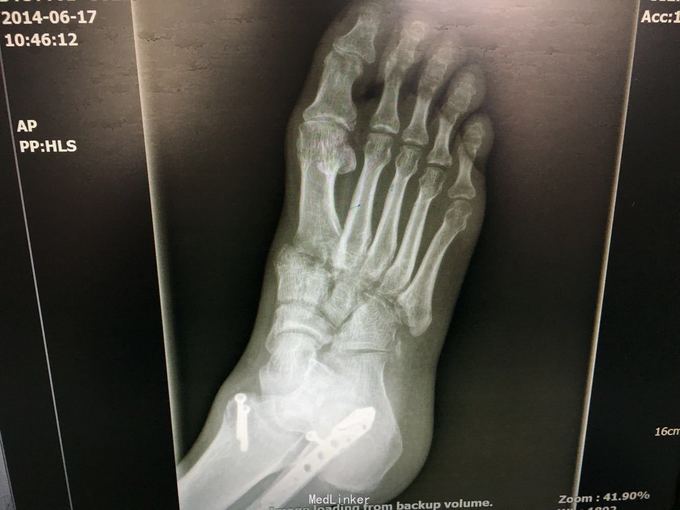

查体:左肾区叩痛,无皮肤隆起,未扪及肿块;腰椎压痛,活动受限,双下肢感觉存在,右小腿石膏托外固定,有踝关节明显肿胀,局部压痛活动受限,指端感觉血运可。 CT及X片:L2、L4椎体爆裂性骨折,L1-L4左侧横突骨折,右坐骨支骨折,右侧胫骨内、后及右侧腓骨外踝骨折,右足第1-4跖骨向外侧脱位及半脱位,伴近端斯脱性骨折。左肾挫裂伤,左肾重度积水,左肾周血肿。

诊断:右足lisfrance损伤,左肾挫裂伤;左肾周血肿,左侧输尿管结石伴左肾重度积水,L2、L4椎体骨折,L1-L4左侧横突骨折,右侧坐骨支骨折,右三踝骨折,全身多处皮肤软组织挫伤 处理:急诊行左肾探查,左肾切除术,择期行经后路腰2、4椎体骨折切开复位、椎公根螺钉内固定术+右内、外踝骨折切开复位内固定术,择期行右足lisfrance关节复位克氏针内固定术。